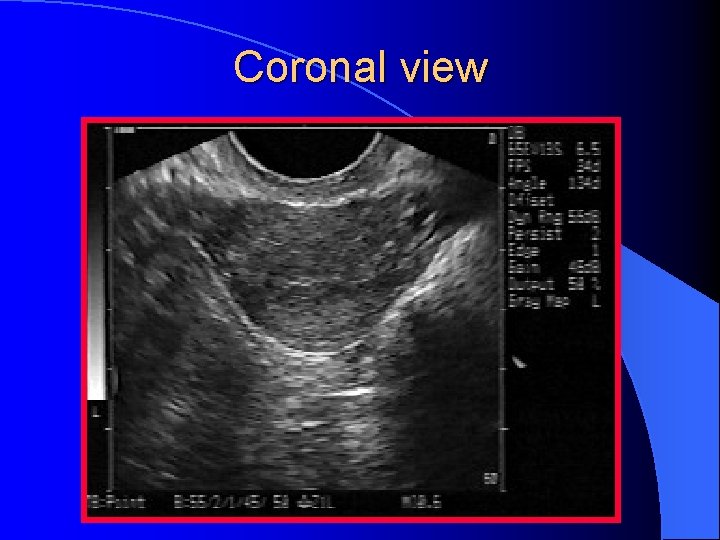

Coronal view